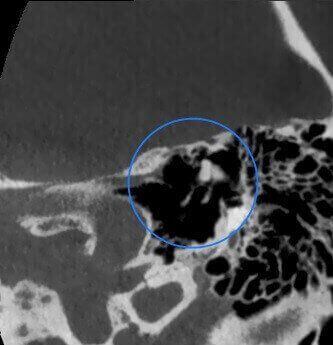

Impianto Cocleare